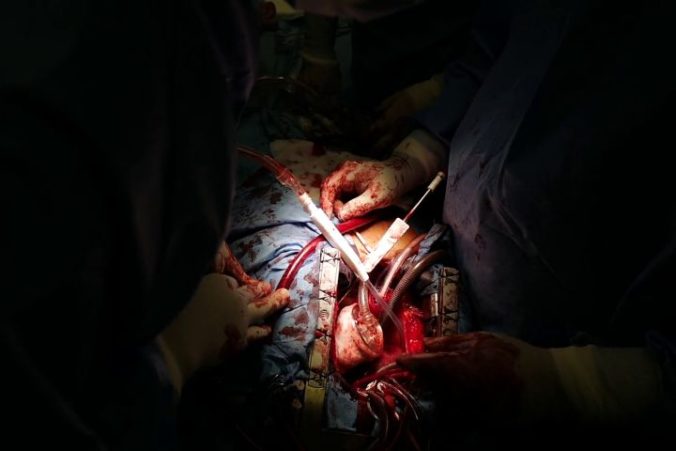

Umelé srdce Zdroj: NÚSCH

Umelé srdce v hrudnom koši Zdroj: NÚSCH

Umelé srdce Zdroj: NÚSCH

Umelé srdce v hrudnom koši Zdroj: NÚSCH

Ľudí, ktorým pre poškodenie srdca ostávajú len hodiny či dni života, majú šancu prežiť vďaka umelému srdcu.